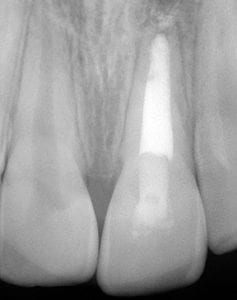

Coneixes el tractament d’endodòncia? Potser, quan reps la noticia de necessitar-ne un et quedis parat i et sorgeixin dubtes i preguntes sobre aquest tipus de